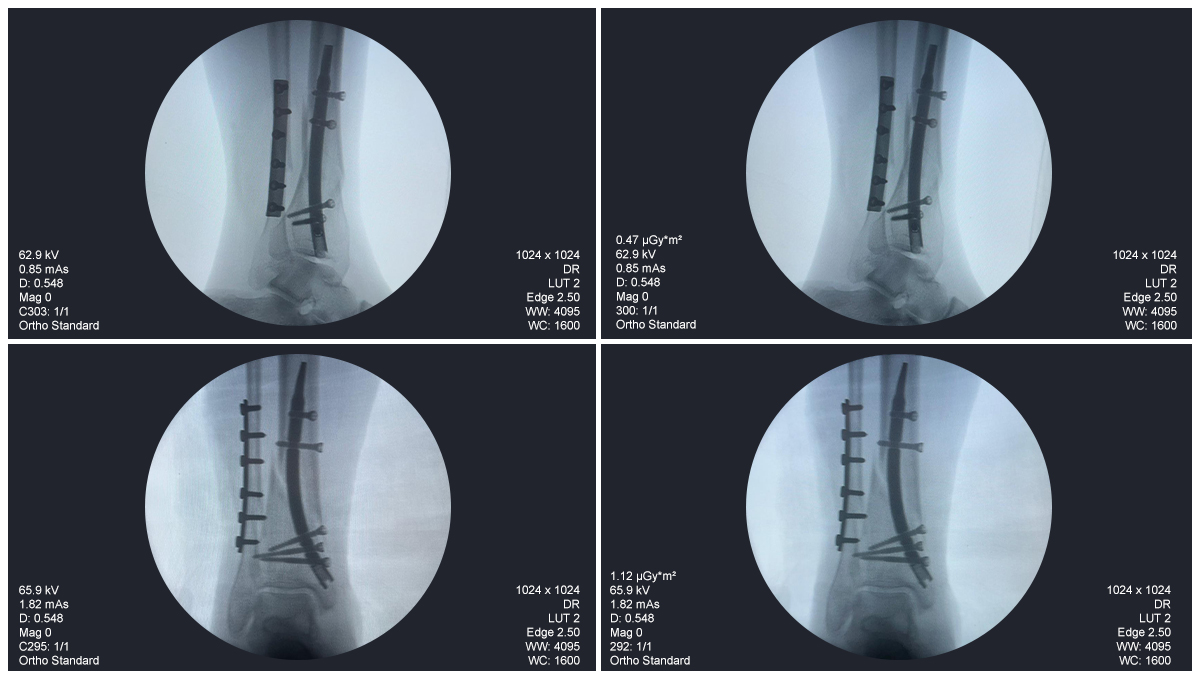

Estudio de caso de fijación de clavo tibial distal con soporte de placa para peroné

Tibia y peroné distales

Clavo tibial distal

Placa de bloqueo del peroné

Radioscopia intraoperatoria con arco en C, vistas AP y lateral

Este caso involucró la fijación de la tibia distal utilizando un clavo tibial distal intramedular. La fluoroscopia intraoperatoria confirmó la posición del clavo, los tornillos de bloqueo distales y la fijación de la placa del peroné.

caso-de-clavo-tibial-distal-paciente-de-31-años-ap-view-czmeditech

clavo-distal-tibial-caso-paciente-de-31-años-vista-lateral-czmeditech